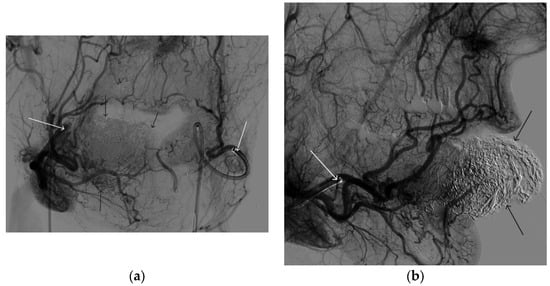

A 35-year-old male patient was admitted to the clinic with complaints of a cosmetic defect in the lower lip area. He has been ill since birth; 18 years ago he was diagnosed with AVM of the lower lip and microsurgical removal was performed. Over the past three years, the growth of formation has been noted. Angiography revealed a relapse of arteriovenous malformation with afferents from the left facial artery (Figure 3). In three years, he underwent several stages of treatment: endovascular embolization with gelatin sponge and embolization with pure ethanol, without effect. The patient underwent endovascular embolization of the AVM of the lower lip with 5 mL of non-adhesive composition ONYX18. Arteriovenous malformation was shut down totally (Figure 4, Figure 5 and Figure 6). The patient was directed to the next stage of surgical treatment—AVM removal by cosmetic surgeons (Figure 7). The mRs score at discharge was 1.

Figure 6. Digital subtraction angiography from the right and left facial arteries: (a) direct projection; (b) lateral projection (white arrows indicate catheters at the ostium of the facial arteries, black arrows indicate embolizate cast). The absence of AVM contrast is noted.

Gels 09 00954 g006